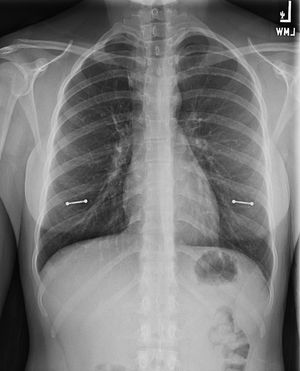

Hereβs an interesting foreign body observed on an X-ray! Or is it foreign at all? Here we have not one, but two dumbbell-shaped foreign bodies overlying the chest π©π© If you know what they are comment below! This is just a friendly reminder that we see EVERYTHING in radiology. Credit: imgur, user: narwallaby